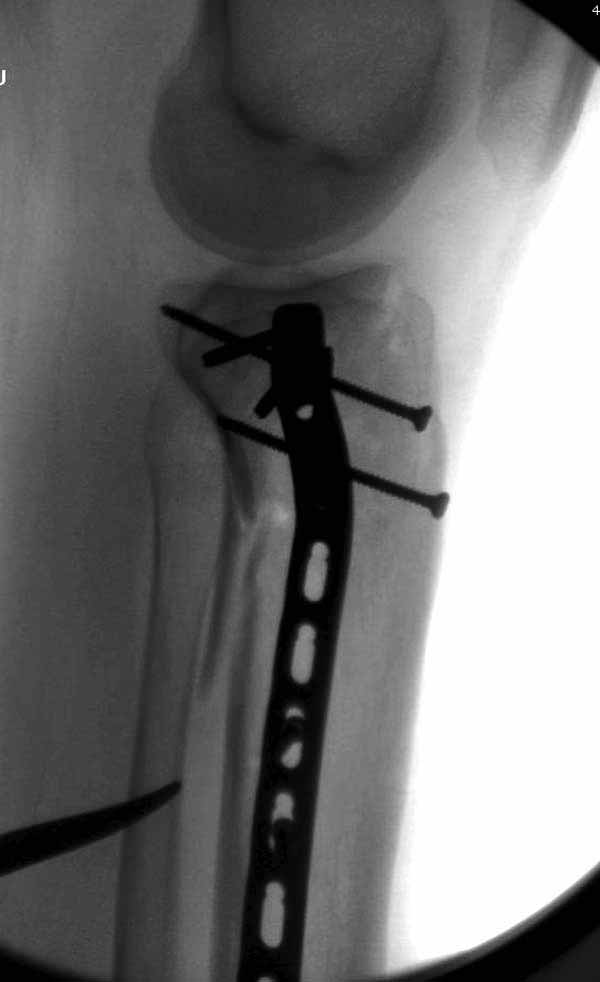

Двухколоннный перелом тибиал плато с вовлечением проксимального диафиза. Внутрисуставной компонент без смещения, и такой перелом можно лечить любым из описанных методов, о которых говорят наши коллеги.

Удобно аппаратом Илизарова или интрамедуллярным гвоздем. Гвозди не так сложно, как пугают, тем более Александр готов помощь с методичкой. Сперва надо установить компрессирующие шурупы на мыщелки. Давно отказались в пользу 3.5-4.0 мм кортикальных вместо толстых спонгиозных, потому что не доказаны преимущества толстых шурупов. Тонкие шурупы в субхондральной зоне смотрятся намного элегантнее, чем толстые 6.5.

Это мероприятие превращает перелом в простой диафизарный, который легко можно фиксировать гвоздем. Шурупы надо установить сзади предполагаемого места введения гвоздя.

Как понял, аппарат Илизарова не рассматривается предпочтительным для фиксации методом, хотя на фоне отека было бы идеальным для данного перелома. Для пластины требуется идеальная кожа, иначе наличие “суперсовременных имплантов” не поможет, и могут развиться серьезные осложнения.

В приложении этапы фиксации Both Column Fx и пластиной Synthes для плеча при переломе медиального мыщелка.